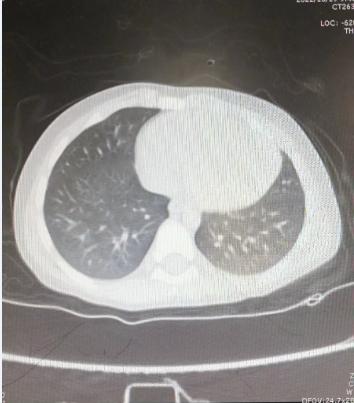

治疗6天后复查肺CT

“睡一觉检查就结束了,孩子也不闹腾,这项技术真好!”奇奇妈妈感叹道。经过治疗,奇奇的病情快速好转并康复出院。